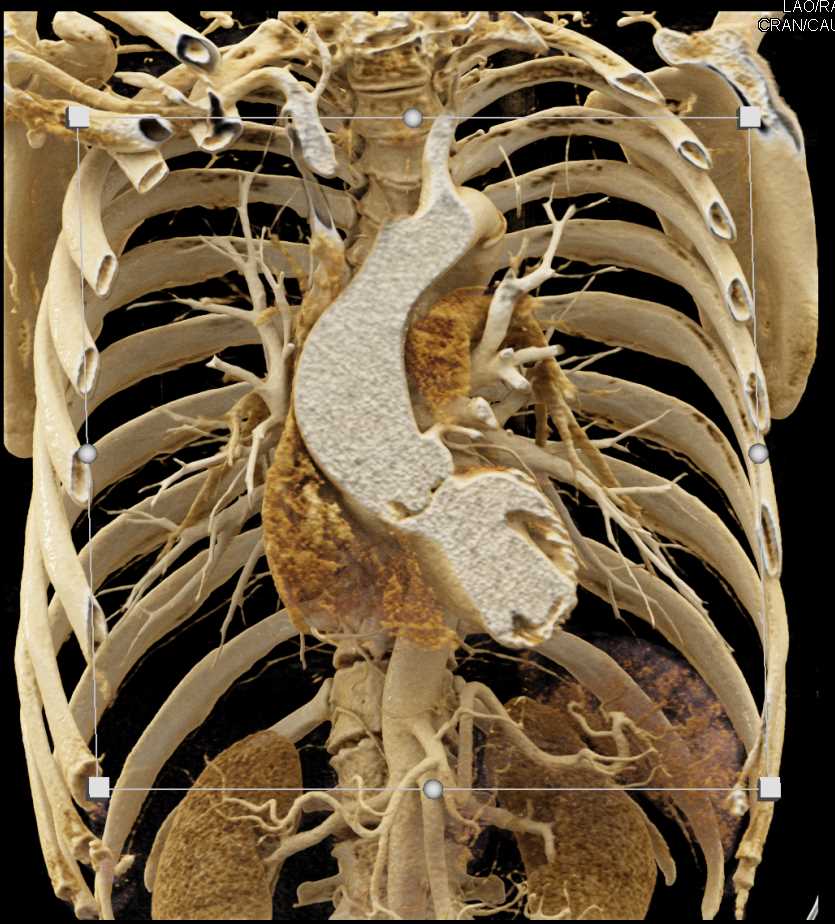

A systematic approach to cardiac pouchings and outpouchings can help radiologists maximize diagnostic accuracy and guide patient management or further workup. bit.ly/42HCBY3 UCLA Radiology Radiology of USC

A systematic approach to cardiac pouchings and outpouchings can help radiologists maximize diagnostic accuracy and guide patient management or further workup. bit.ly/42HCBY3 <a href="/RadiologyUcla/">UCLA Radiology</a> <a href="/RadiologyUSC/">Radiology of USC</a>